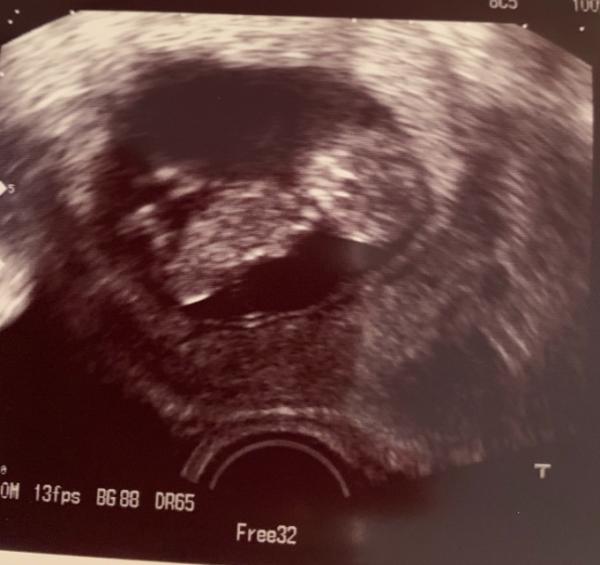

Hallo ihr Lieben, ich wollte euch kurz von meinen Arzttermin berichten! Ich musste mich ja leider 3,5 Wochen gedulden, da mein Doc 3 Wochen Urlaub hatte. Ich war echt etwas nervös, aber es ist alles super! Herzchen schlägt, Baby turnt fleißig herum und ist auf dem Tag genau 11+5 entwickelt! Anbei auch ein kleines Bildchen! Ich bin so erleichtert, aber nun ist meine kleine Tochter krank und liegt mit Fieber und Schnupfen im Bett. Freitag gehts dann in den Urlaub und wir erholen uns erstmal alle. Ganz liebe Grüße an euch alle!

Bild zu Heute endlich wieder beim Arzt gewesen... - Forum für Januar - Mamis